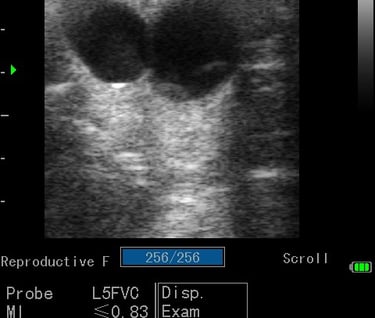

Gynécologie